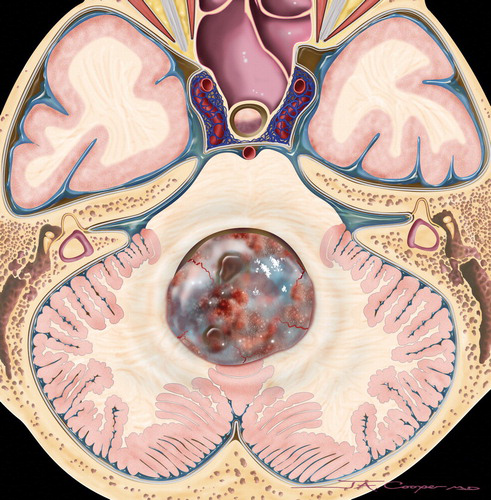

髓母细胞瘤 是位于小脑的脑肿瘤,小脑是控制平衡,协调和其他复杂运动功能的大脑部分。髓母细胞瘤较常生长在小脑的中央部位,而在小脑的外部部分则...

髓母细胞瘤 是儿童中较常见的恶性脑肿瘤。根据定义,髓母细胞瘤发生在小脑中,小脑是位于头骨基部的脑部的一部分,位于脑干上方。小脑参与许多功能...

髓母细胞瘤 是一种癌性脑肿瘤。它在小脑中发育,小脑是头骨底部附近的大脑的一部分。髓母细胞瘤可以扩散到中枢神经系统 (大脑和脊髓)。儿童大多...

髓母细胞瘤,这种起源与胚胎残余细胞的肿瘤可发生在脑组织的任何部位,但多数生长在四脑室顶之上的小脑蚓部,是中枢神经系统恶性程度较高的肿瘤之...

累及小脑中线结构的肿瘤有髓母细胞瘤、室管膜瘤、皮样囊肿和蛛网膜囊肿。对于少数允许自发性通气的病人,使用短效吸入麻醉剂,通过改变吸入二氧化碳...

髓母细胞瘤是后颅窝比较常见的恶性肿瘤,也是中枢神经系统恶性程度较高的神经上皮性肿瘤之一。它的细胞形态很像胚胎时期的髓母细胞,因此得名。髓母...